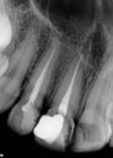

antes depois